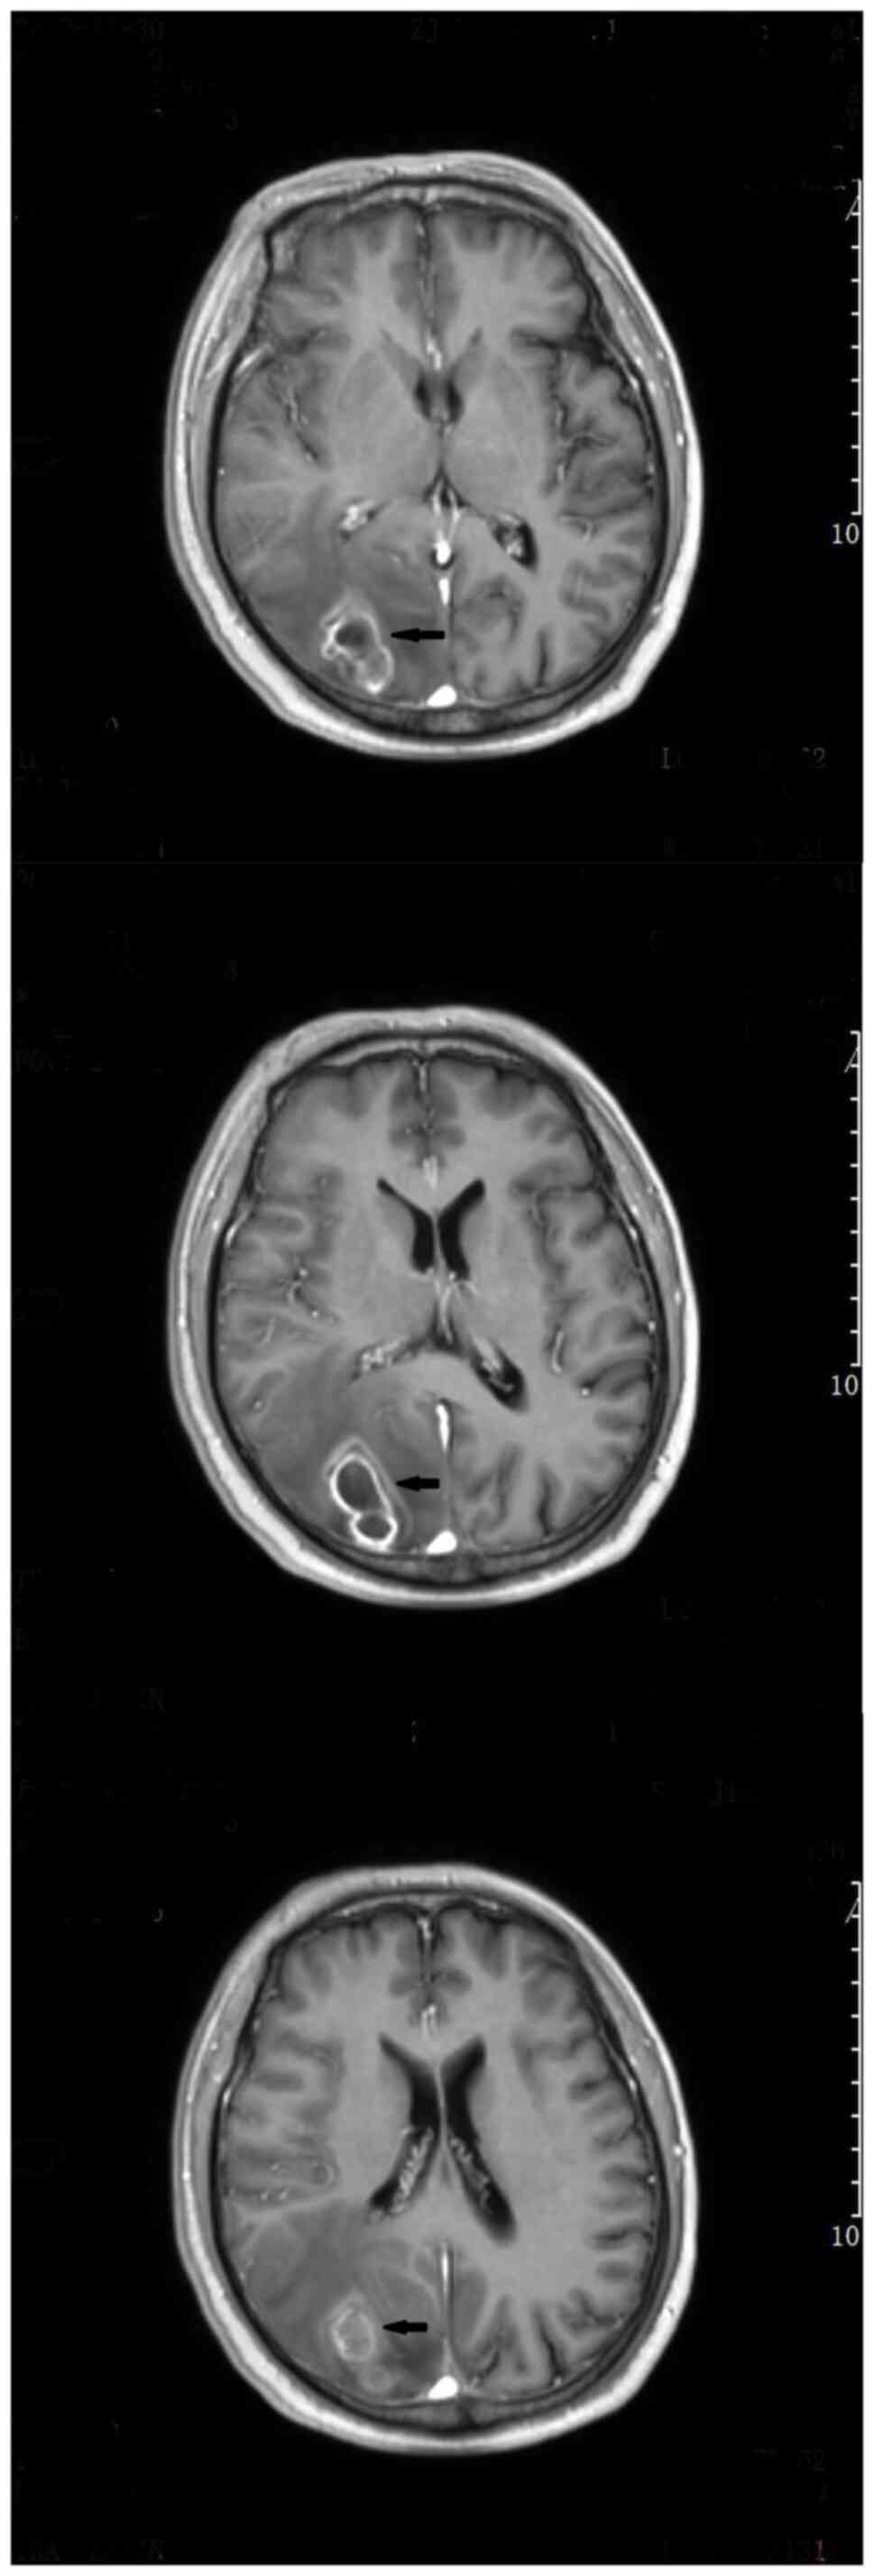

After being treated with voriconazole (0.2 g; Q12 h) for two straight weeks, the patient recovered well, with the body temperature back to normal range. The follow-up CT brain imaging results were also found satisfactory (Fig. 4). Since the patient required further chemotherapy, he was referred to the hematology department of The First People's Hospital of Huzhou for further anti-infective therapy. Voriconazole was used for intensive treatment (0.2 g; Q12 h) in the first 3 months. Following that, the patient's temperature was normal and his condition was generally stable and the patient has now entered maintenance treatment (0.1 g; Q12 h). No additional PCR or NGS tests were performed following surgery, cerebrospinal fluid test and enhanced head MRI were reviewed in June 13, 2023. Fortunately, the patient's head MRI (enhanced T1) showed no obvious enhancement of the disease (Fig. 5). There was no increase in micrototal protein (Pyrogallol red colorimetry) and no decrease in sugar content in cerebrospinal fluid test, suggesting that there was no abnormal index of cerebrospinal fluid infection. Although it cannot be ruled out that the patient has a recessive Aspergillus infection, treatment is still effective at the time of writing. In the later stage, the authors recommend that patients undergo NGS testing of cerebrospinal fluid to further determine whether there is a recurrence of Aspergillus.

Figure 5

Head magnetic resonance imaging (enhanced T1) of the patient was performed at 7 months after surgery. The arrows in the picture indicate no obvious enhancement of the disease.